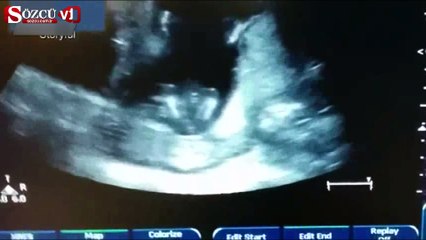

Ultrasonda ilginç anlar: Anne şarkı söyle, bebek alkış tuttu

Anne karnındaki bir bebek, anne ve babasının şarkı söylemesi üzerine alkış tutmaya başladı